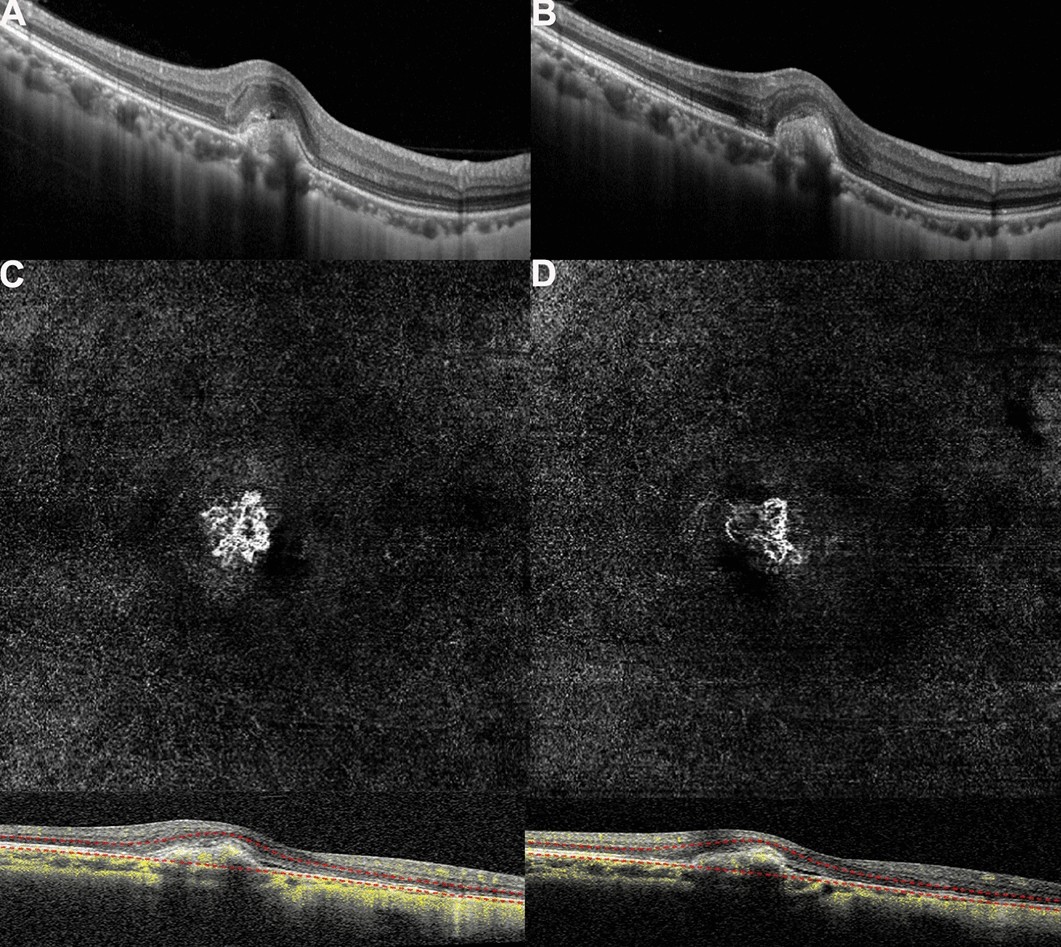

Figure 4

(A,B) Optical coherence tomography (OCT) images of a patient with myopic macular neovascularization (mMNV) before and after receiving conbercept. Central macular thickness (CMT) decreased from 281.63 to 261.22 μm, and the hyperreflective signal lesions in the outer layer of the retina decreased. (C,D) Optical coherence tomography angiography (OCTA) images of the patient. MNV in both figures shows a small, vascular chaotic high-flow vascular network with a tree bud shape. The MNV areas in (C) and (D) are 0.54 and 0.23 mm2, while the blood vessel areas are 0.23 and 0.13 mm2, respectively.